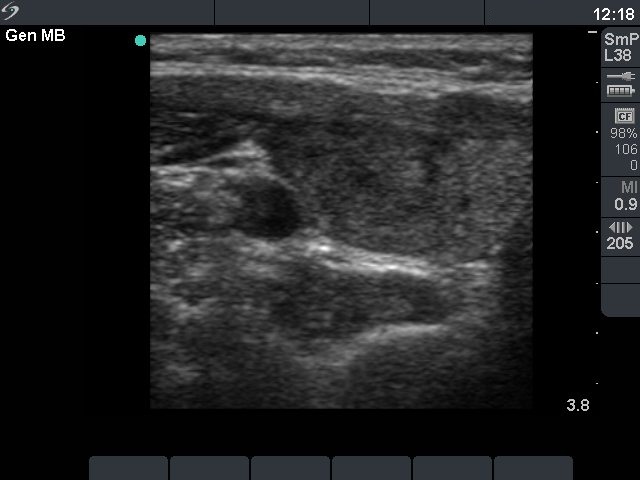

Ultrasonography: revealed a moderately hypoechogenic nodule with a halo sign in the right lobe. The dimensions of the right nodule increased from 13x10x18 mm to 21x16x30 mm over 5 years.